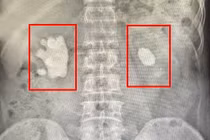

Sỏi lớn, sỏi san hô bắt buộc phải phẫu thuật. Để lâu sỏi sẽ tàn phá, làm mất chức năng thận, gây ra nhiễm trùng thận nguy hiểm tính mạng của người bệnh.

Sỏi san hô nếu không điều trị sẽ tàn phá làm mất chức năng thận, gây ra những đợt nhiễm trùng thận tái đi tái lại, đôi khi nhiễm trùng nặng, có thể gây nguy hiểm tính mạng.